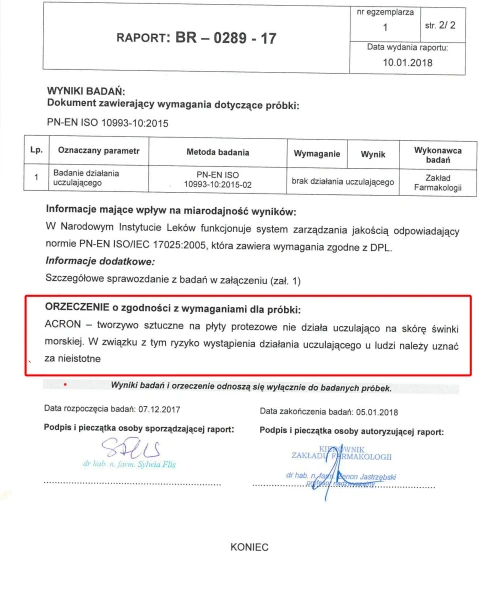

BRAK UCZULEŃ I PODRAŻNIEŃ

ACRON został gruntownie przebadany i przetestowany. Badania Narodowego Instytutu Leków wykazały, że nie zawiera substancji toksycznych i drażniących. Jest bezpieczny dla pacjentów i personelu medycznego.

DLA ALERGIKÓW